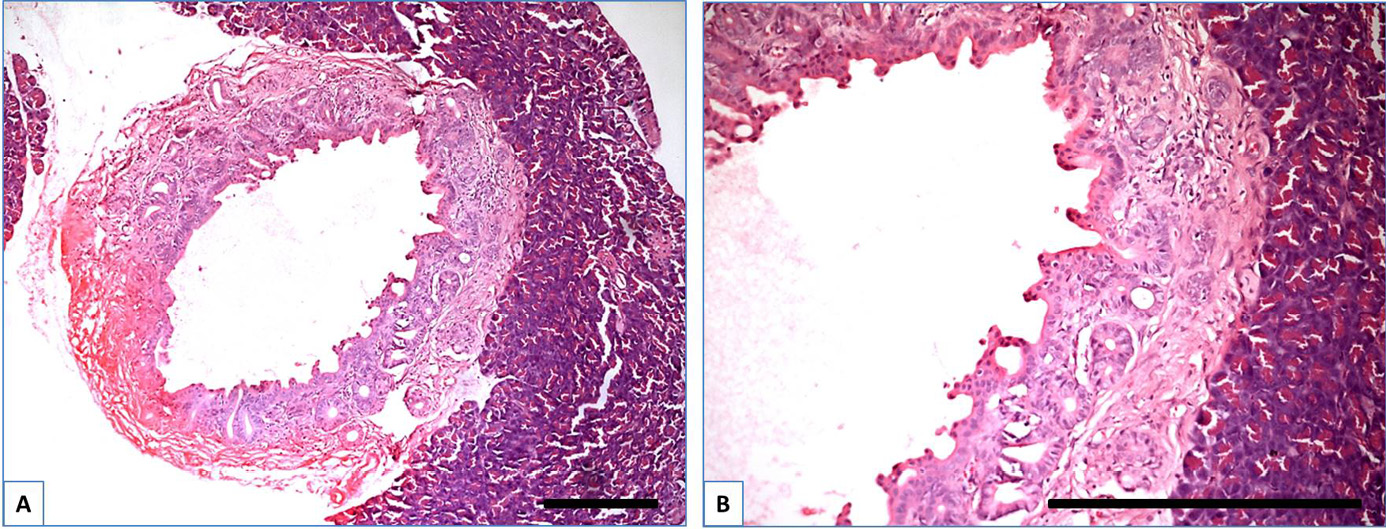

Histopathological observation included both ductal and acinar parts of the pancreas. Changes in the ductal part were classified according to the PanIN grading system.33 In the control group, the ductal part (Figure 1) was characterized by the typical structure of a simple cuboidal epithelium. In the CP group (Figure 1), most ducts were surrounded by developed connective tissue stromal elements, which in some samples could be classified as an early stage of fibrosis (also around the vascular part). The presence of immune cell infiltration (the most common cells are neutrophils and macrophages) in the expanded stromal part of the round ducts also indicated the intervention of a low degree of chronic inflammation. Ductal cells in the CP group (Figure 2) in all samples changed their shape from cuboidal to prismatic; in some of them, active proliferation with a dysplastic process was observed, which led to the appearance of glandular epithelium in the thickened wall of the duct. These changes stimulated the epithelium for invagination. This type of pacreas lesion manifestation is classified as a PanIN-1A - PanIN-1B according to the established grading system.

In the CP + DM group, in some samples with pronounced dysplasia, the ductal part exhibited the previously described features (Figure 1). The ductal epithelium was frequently transformed into a pseudostratified type (Figure 3) and pseudopapillary structures were formed within the wall (Figure 3B). Additionally, villous-like structures were observed in the duct lumen (Figure 3C), indicating a high-grade PanIN-2 and PanIN-3.